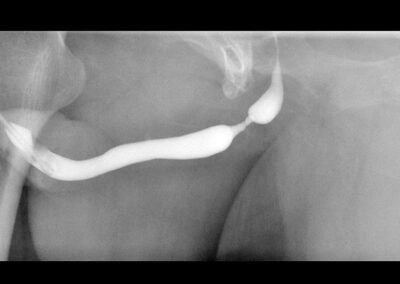

Eine Harnröhrenstriktur wird zuerst radiologisch dargestellt, um den Grad der Enge und deren Länge zu definieren. Gleichzeitig wird deren Lokalisation studiert, um die Operation besser zu planen.

Harnröhre: Harnröhrenenge — Schlitzung